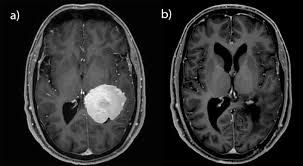

Meningeome Neurochirurgie Inselspital Bern